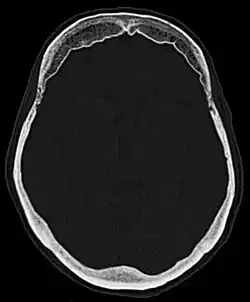

Hyperostosis frontalis interna in a 74-year-old woman

Hyperostosis frontalis at CT